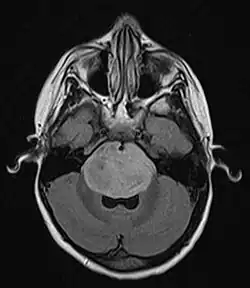

| Brain stem glioma. MRI axial, with contrast | |

Neuroimaging, such as MRI, is the main diagnostic tool for brain stem gliomas. In very rare cases, surgery and biopsy are performed.